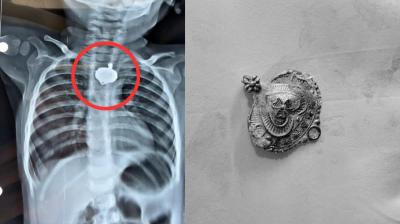

बड़वानी में 9 माह के बच्चे की आहार नली में फंसा मंगलसूत्र, डेढ़ महीने बाद एक्स-रे से खुलासा

24 Nov, 2025 08:30 AM IST | SAMNALIVE.COM

बड़वानी: रविवार को जिला अस्पताल में एक बेहद संवेदनशील और हैरान करने वाला मामला सामने आया. जब 9 माह के एक बच्चे के गले में मंगलसूत्र फंसा हुआ देखा गया. घटना...